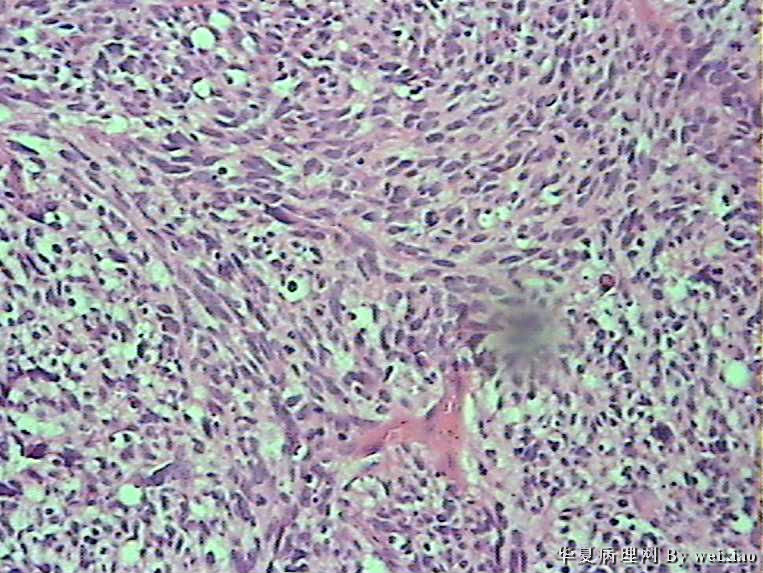

病史:男45岁,头痛2个月,手术所见:额叶占位性病变,与周围正常脑组  织的界限不清。

大体:灰白色碎组织一堆,质软,大小:2.5*1.8*1.3cm

• 额叶肿瘤图1

图1

×参考诊断

胶质母细胞瘤

坏死+细胞密度+异性+围绕血管现象。

考虑血管外皮瘤

脑膜瘤,查看核分裂和肿瘤侵犯程度。

不典型脑膜瘤

血管外皮瘤,SFT.

会诊胶质母细胞瘤

The tumor cells are kind of spindle, need to rule out gliosarcoma, you need to check MRI films, do immunostain for GFAP, and vimentin. The vascular proliferation (VP) supports GBM.

肿瘤细胞呈梭形,血管增生明显,有坏死,符合胶质母。